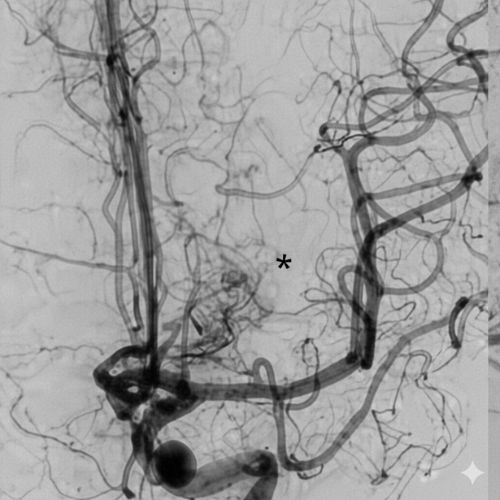

Aneurismas Cerebrales

También conocido como aneurisma intracraneal o intracerebral, es un punto débil o fino en un vaso sanguíneo cerebral que sobresale como un balón y se llena de sangre.

Malformaciones Arteriovenosas

Defectos del sistema circulatorio que ocurren por lo general durante el desarrollo del embrión o poco después del nacimiento.